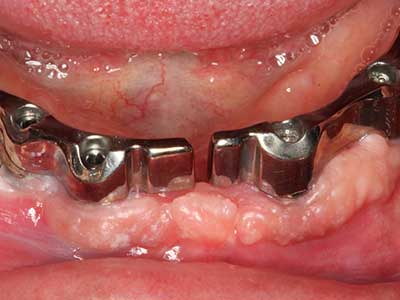

Когато се извършват хирургични процедури върху кост в непосредствена близост до чувствителни структури като кръвоносни съдове или нерви, ротиращите инструменти създават значителен риск за ятрогенно нараняване. Пиезоелектрическите апарати могат да бъдат от помощ при препарация на костно покритие и отстраняване на твърда кост близо до нерви, особено за оголване на нервите след ятрогенно нараняване, както и по време на латерализация на нервите за резекционни и реконструктивни процедури или поставяне на имплант (Фиг. 17-20). Лекият контакт между пиезонакрайника и нерва по принцип не води до нараняване, но ако действате непредпазливо с трионообразни движения или приставки за остатъчен костен субстрат, може да причините временно или перманентно увреждане на нерва. Въпреки това, рискът от увреждане се счита за много по-малък, отколкото при употреба на триони или ротиращи инструменти (Pereira, Gealh et al. 2014).